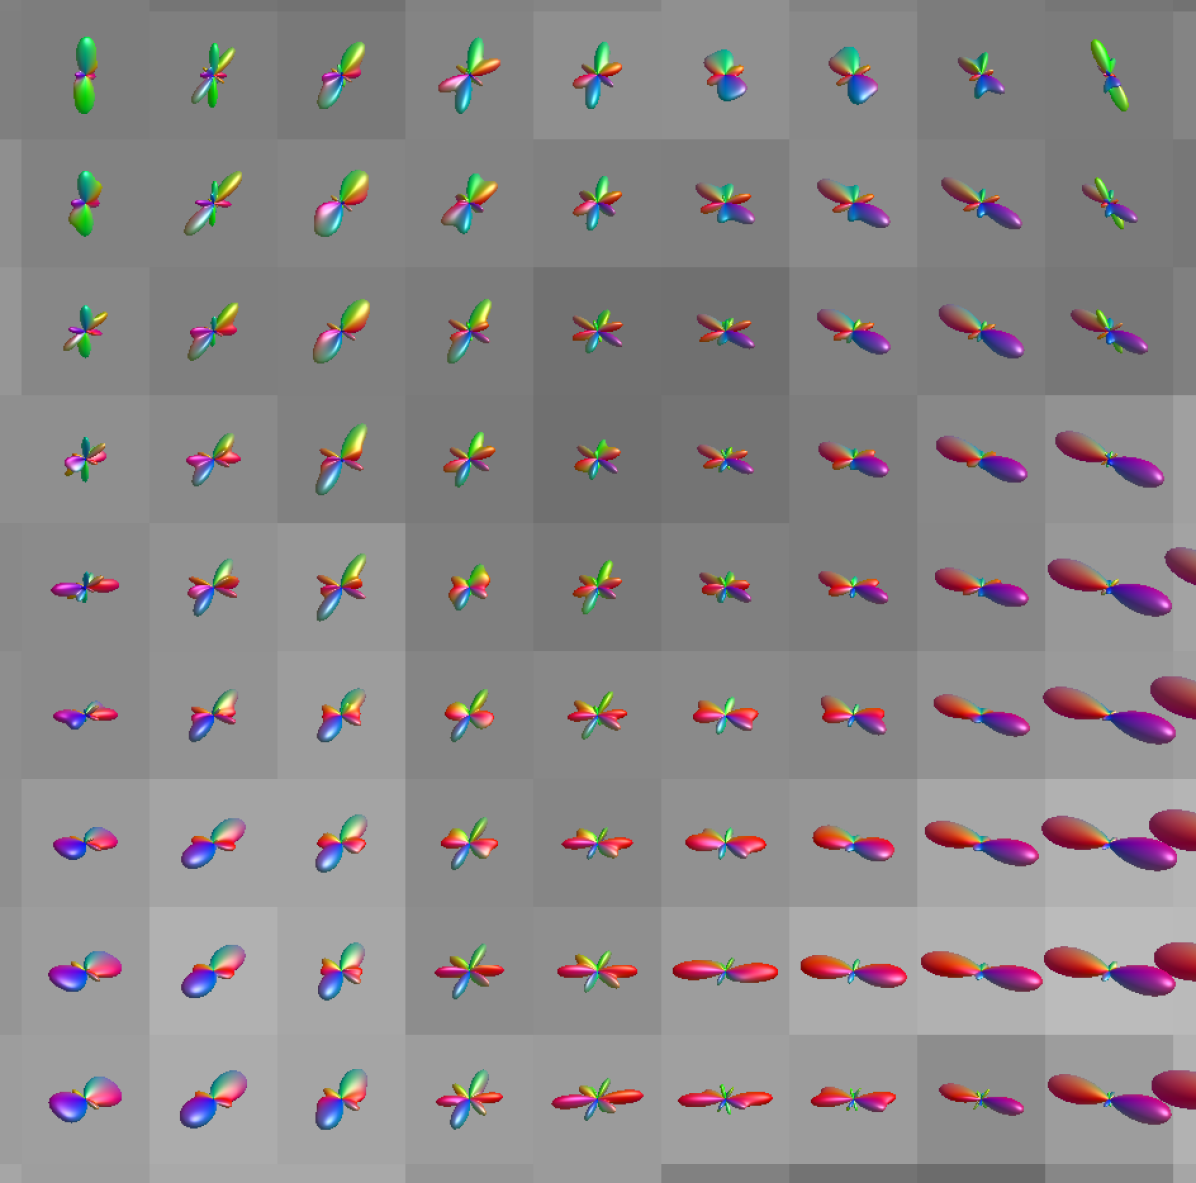

Refer to captiong7,1(𝐞;𝜽)subscript𝑔71𝐞𝜽g_{7,1}(\mathbf{e};\bm{\theta})g10,1(𝐞;𝜽)subscript𝑔101𝐞𝜽g_{10,1}(\mathbf{e};\bm{\theta})g17,3(𝐞;𝜽)subscript𝑔173𝐞𝜽g_{17,3}(\mathbf{e};\bm{\theta})g24,10(𝐞;𝜽)subscript𝑔2410𝐞𝜽g_{24,10}(\mathbf{e};\bm{\theta})g36,10(𝐞;𝜽)subscript𝑔3610𝐞𝜽g_{36,10}(\mathbf{e};\bm{\theta})

Figure 2: Visualisation of kernel weights sampled from gc,k(𝐞;𝜽)subscript𝑔𝑐𝑘𝐞𝜽g_{c,k}(\mathbf{e};\bm{\theta}) within a PCConv layer, where c𝑐c and k𝑘k index the input and output feature dimensions respectively. To generate the spheres, drsubscript𝑑𝑟d_{r} is varied whilst all other components of 𝐩𝐩\mathbf{p} are kept constant.

Here pmsubscript𝑝𝑚p_{m} is the m𝑚mth component of the coordinate vector 𝐩E𝐩superscript𝐸\mathbf{p}\in\mathbb{R}^{E} given by 𝐩=[uiuj,vivj,wiwj,ρiρj,dr]𝐩subscript𝑢𝑖subscript𝑢𝑗subscript𝑣𝑖subscript𝑣𝑗subscript𝑤𝑖subscript𝑤𝑗subscript𝜌𝑖subscript𝜌𝑗subscript𝑑𝑟\mathbf{p}=[u_{i}-u_{j},v_{i}-v_{j},w_{i}-w_{j},\rho_{i}-\rho_{j},d_{r}]. We have opted to enforce rotational invariance across the sphere by omitting ϑitalic-ϑ\vartheta and φ𝜑\varphi directly, and instead use p5=dr(ϑj,φj,ϑi,φi)subscript𝑝5subscript𝑑𝑟subscriptitalic-ϑ𝑗subscript𝜑𝑗subscriptitalic-ϑ𝑖subscript𝜑𝑖p_{5}=d_{r}(\vartheta_{j},\varphi_{j},\vartheta_{i},\varphi_{i}) where dr(ϑj,φj,ϑi,φi)=sin(ϑj)sin(ϑi)+cos(ϑj)cos(ϑi)cos(φjφi)subscript𝑑𝑟subscriptitalic-ϑ𝑗subscript𝜑𝑗subscriptitalic-ϑ𝑖subscript𝜑𝑖subscriptitalic-ϑ𝑗subscriptitalic-ϑ𝑖subscriptitalic-ϑ𝑗subscriptitalic-ϑ𝑖subscript𝜑𝑗subscript𝜑𝑖d_{r}(\vartheta_{j},\varphi_{j},\vartheta_{i},\varphi_{i})=\sin(\vartheta_{j})\sin(\vartheta_{i})+\cos(\vartheta_{j})\cos(\vartheta_{i})\cos(\varphi_{j}-\varphi_{i}). The function γ:2L:𝛾superscript2𝐿\gamma:\mathbb{R}\rightarrow\mathbb{R}^{2L} is a Fourier feature mapping motivated by Tancik et al. [35] and Mildenhall et al. [27] which is used to improve the hypernetwork’s ability to learn high-frequency functions. In practice, L𝐿L is a hyperparameter of the PCConv layer. Figure 2 provides examples of weights sampled from a trained PCConv layer with varying drsubscript𝑑𝑟d_{r}. The channels selected within the Figure demonstrate a variety of functions across the sphere, highlighting the network’s ability to learn both high and low frequency kernels.